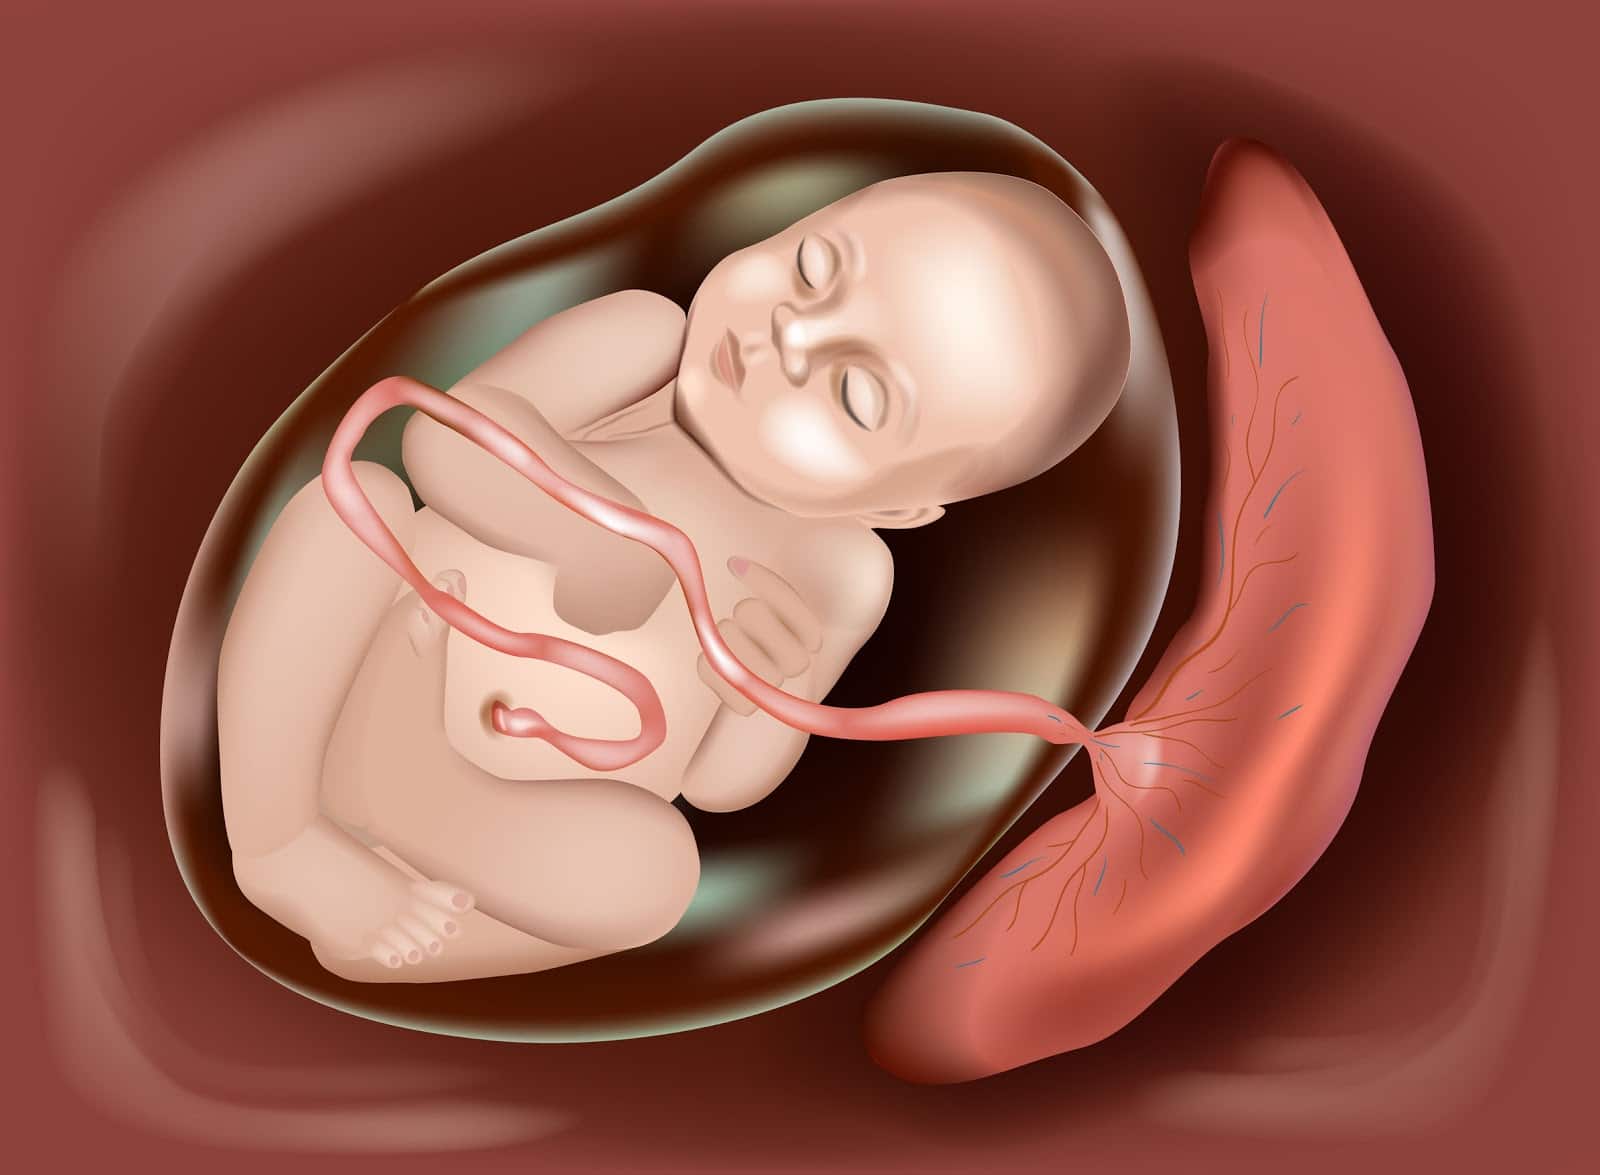

در دوران بارداری، جفت یکی از مهمترین اعضای موقتی بدن مادر است که وظیفه تغذیه، اکسیژن رسانی و دفع مواد زائد جنین را بر عهده دارد. جفت معمولا به دیواره بالایی یا کناره های رحم میچسبد، اما گاهی در جلوی رحم و نزدیک دهانه رحم قرار میگیرد که به آن جفت قدامی (Anterior Placenta) میگویند. این وضعیت کاملا طبیعی است و در حدود ۳۰ تا ۵۰ درصد بارداری ها دیده میشود، اما چون جفت در جلوی رحم قرار دارد، ممکن است برخی احساسات و علائم متفاوتی برای مادر ایجاد کند. امروز در پارسی دی و در ادامه همه چیز را درباره جفت قدامی توضیح میدهم.

جفت قدامی یعنی جفت در قسمت جلوی رحم قرار گرفته و به دیواره جلویی آن چسبیده است. این وضعیت معمولا کاملا طبیعی است و مشکل خاصی ایجاد نمیکند. فقط به دلیل اینکه جفت بین جنین و دیواره شکم قرار میگیرد، ممکن است مادر حرکات جنین را کمی دیرتر یا ضعیف تر احساس کند. جفت قدامی به تنهایی خطرناک نیست و تنها در صورتی اهمیت پیدا میکند که خیلی پایین باشد و به دهانه رحم نزدیک شود. در بیشتر بارداری ها، جفت قدامی بدون هیچ نگرانی خاصی ادامه پیدا میکند.

جفت قدامی یعنی جفت به دیواره جلویی رحم (سمت شکم مادر) چسبیده باشد، نه به دیواره پشتی (نزدیک ستون فقرات) یا کناره ها. این وضعیت در سونوگرافی به راحتی تشخیص داده میشود. جفت قدامی معمولا مشکلی برای مادر و جنین ایجاد نمیکند و یک حالت طبیعی و شایع است. تنها تفاوت اصلی آن با جفت خلفی این است که لایه جفت بین جنین و شکم مادر قرار میگیرد و به همین دلیل ممکن است حرکت های جنین دیرتر یا ضعیف تر احساس شود.